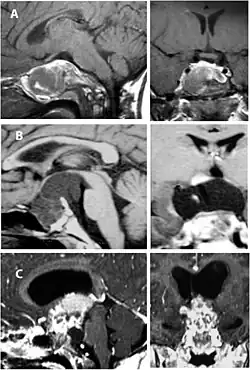

Imaging scans for craniopharyngioma

A physician can conduct a few scans and tests to diagnose a person with craniopharyngioma.[19] High-resolution magnetic resonance imaging (MRI) is commonly used as a diagnostic tool; however, computer tomography (CT) remains the gold standard imaging choice for craniopharyngioma diagnosis as it can detect the severity of the calcification within the tumour.[20]

In some cases, a powerful 3T (Tesla) MRI scanner can help define the location of critical brain structures affected by the tumor. The histologic pattern consists of nesting of squamous epithelium bordered by radially arranged cells. It is frequently accompanied by calcium deposition and may have a microscopic papillary architecture. A computed tomography (CT) scan is also a good diagnostic tool, as it detects calcification in the tumor.[21]

In the adamantinomatous type, calcifications are visible on neuroimaging and are helpful in diagnosis.

The papillary type rarely calcifies. A vast majority of craniopharyngiomas in children are adamantinomatous, whereas both subtypes are common in adults. Mixed-type tumors also occur.[25]

On macroscopic examination, craniopharyngiomas are cystic or partially cystic with solid areas. On light microscopy, the cysts are seen to be lined by stratified squamous epithelium. Keratin pearls may also be seen. The cysts are usually filled with a yellow, viscous fluid rich in cholesterol crystals. Of a long list of possible symptoms, the most common presentations include headaches, growth failure, and bitemporal hemianopsia.